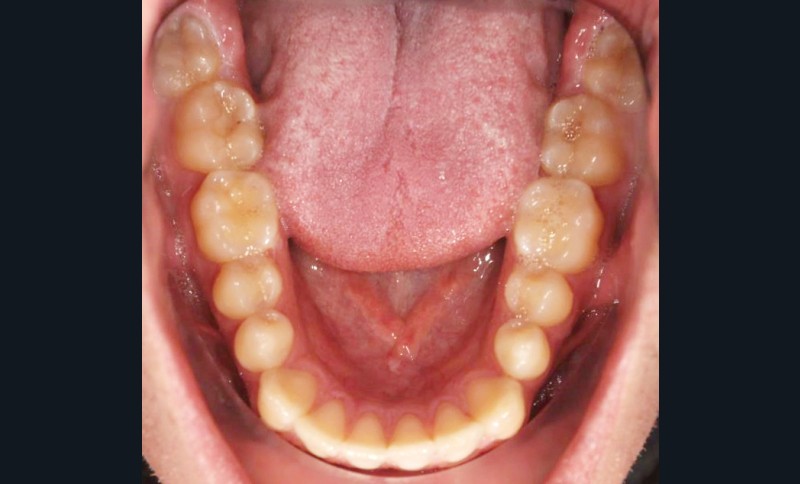

En intra-arcades (fig. 4-6), on note une classe III molaire et canine (fig. 4-5), trois plans d’occlusion, une déviation des milieux d’origine mandibulaire et un inversé articulé du bloc incisif maxillaire ; le biotype parodontal est fin, et l’on note des récessions gingivales (12, 13, 23, 33, 43) certainement dues à la mauvaise position et aux forces mal réparties lors de la mastication (fig. 5). L’arcade maxillaire est carrée avec une DDM antérieure (fig. 7), l’arcade mandibulaire étroite et allongée (fig. 8).